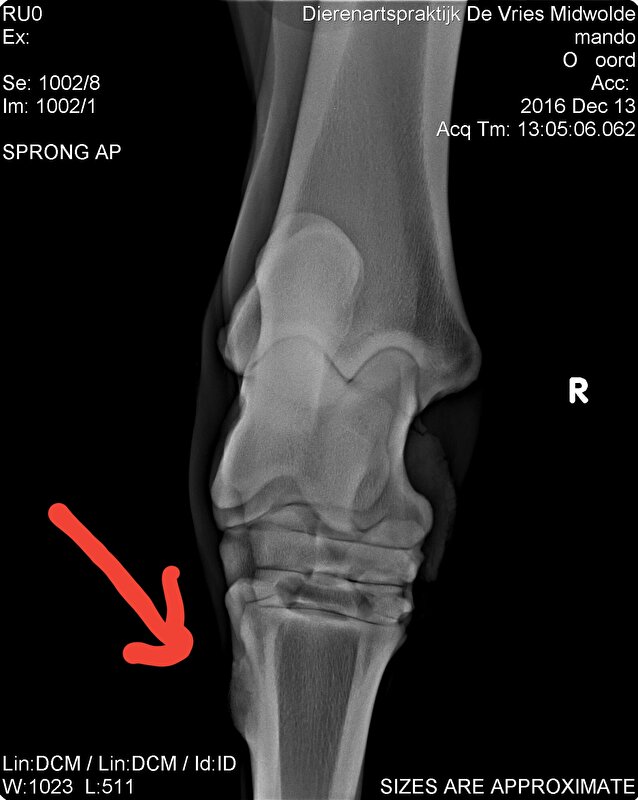

Ook had ik het gevoel dat hij soms niet lekker liep.

Niet kreupel maar ook niet rad.

December op de foto laten zetten en hij is punt gaaf op een schiefel na die hem dus soms irriteert.

Nu gewoon genieten en zien hoe hij per dag is.

Voelt het goed dan lekker trainen voelt het minder dan stapje terug.